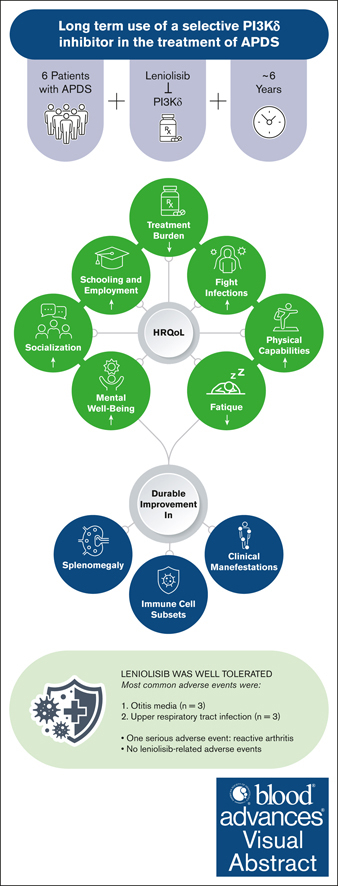

Visual Abstract